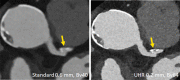

Novel photon-counting detector CT (PCD-CT) has the potential to address the limitations of previous CT systems, such as insufficient spatial resolution, limited accuracy in detecting small low-contrast structures, or missing routine availability of spectral information. In this review article, we explain the basic principles and potential clinical benefits of PCD-CT, with a focus on recent literature that has grown rapidly since the commercial introduction of a clinically approved PCD-CT.